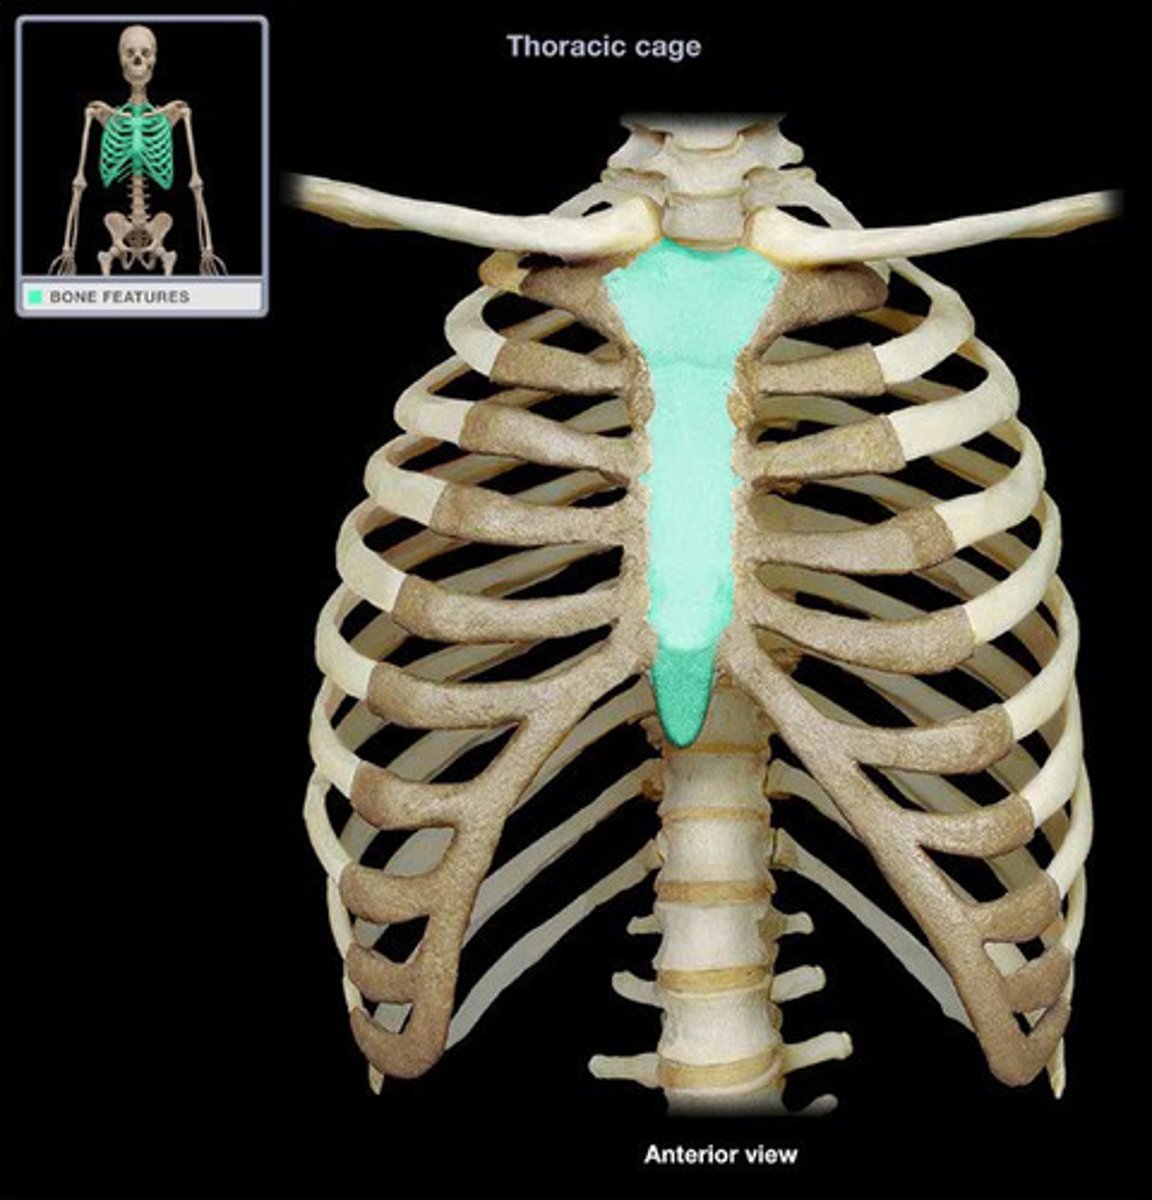

Vertebrosternal Ribs

False Ribs

Floating Ribs

Sternum

Manubrium

Body

Xiphoid Process